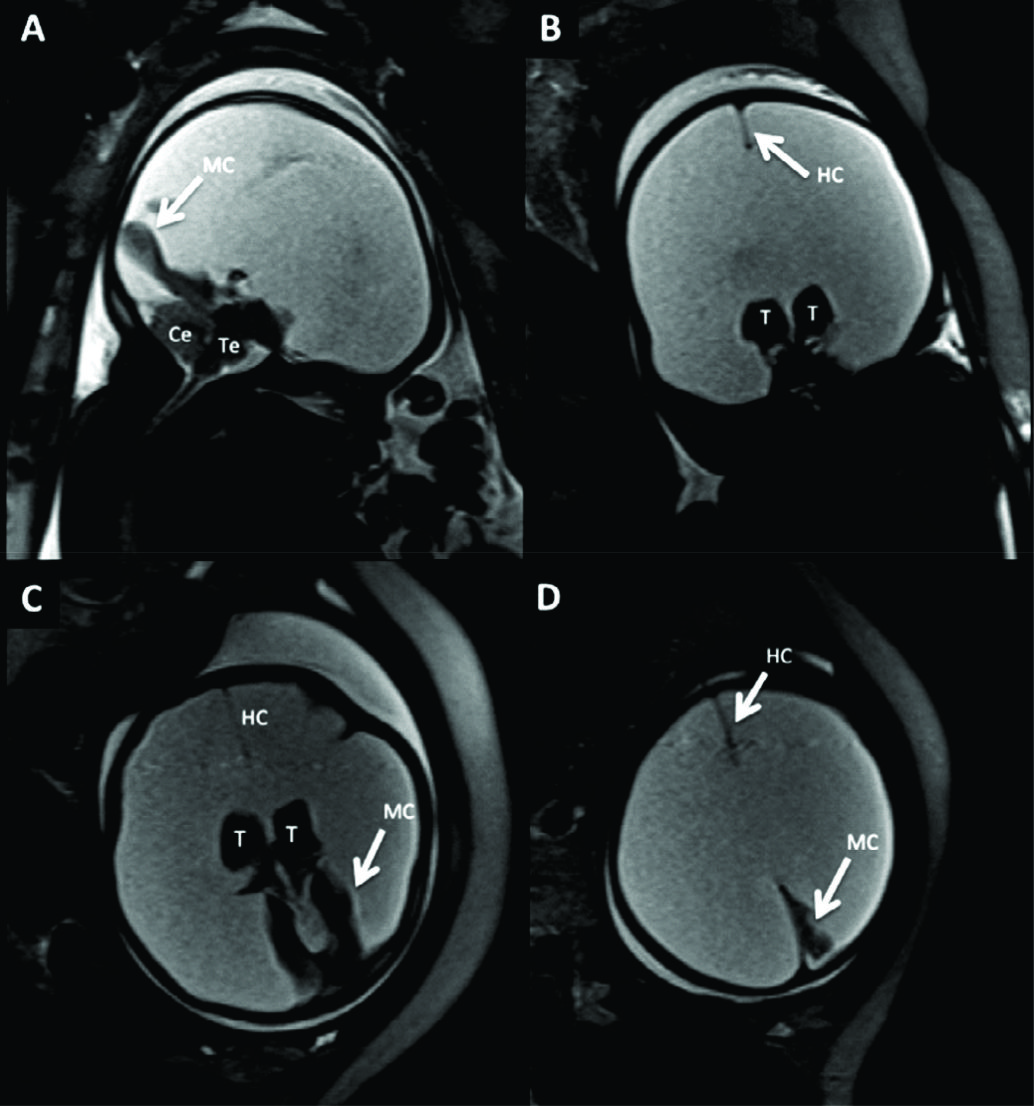

Figura 5

RM Fetal Hidranencefalia.

RMf a las 29 semanas de edad gestacional en paciente referido para confirmación de hidranencefalia, diagnóstico diferencial de HCF extrema. En A imagen sagital donde se observa la dilatación del sistema ventricular con estructuras de la fosa posterior de anatomía normal al igual que el IV ventrículo.

En B imagen coronal donde se observa la severa dilatación de los ventrículos laterales y se observan ambos tálamos (T) de aspecto normal con 3er ventrículo entre ellos.

En los cortes axiales (C y D) se observan los elementos ya destacados y además se corrobora otra estructura de línea media como la hoz cerebral (HC) y la presencia de escaso manto cerebral a nivel occipital (MC). Esto permite diferenciar esta entidad de las prosencefalias. Te: Tronco encefálico Ce: Cerebelo